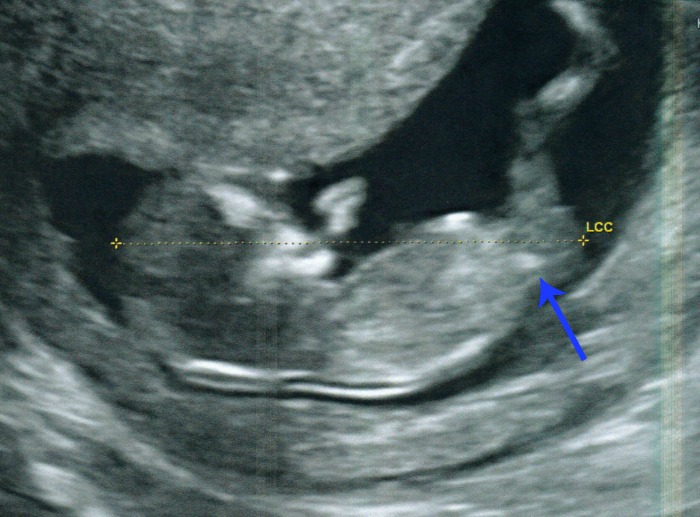

- Several times I saw a clear, long white nub... it was very straight and seemed longer than any of the other nub pictures on here. Not sure what long nub means?

- Numerous times I saw, in profile view, what looked like two white parallel lines. Both lines were shorter than the nub mentioned above but in the same place.

Unfortunately I dont have a clear picture of them but in the following picture you can see them but a bit fuzzy;

Here is another although this looks a little like 3 lines!

I am fairly sure that potty shots dont mean anything but here is the one we have anyway.... they were not checking sex here but measuring leg bone. Part of me thinks there is nothing there and when I look again it looks like a little turtle - am I going mad?!